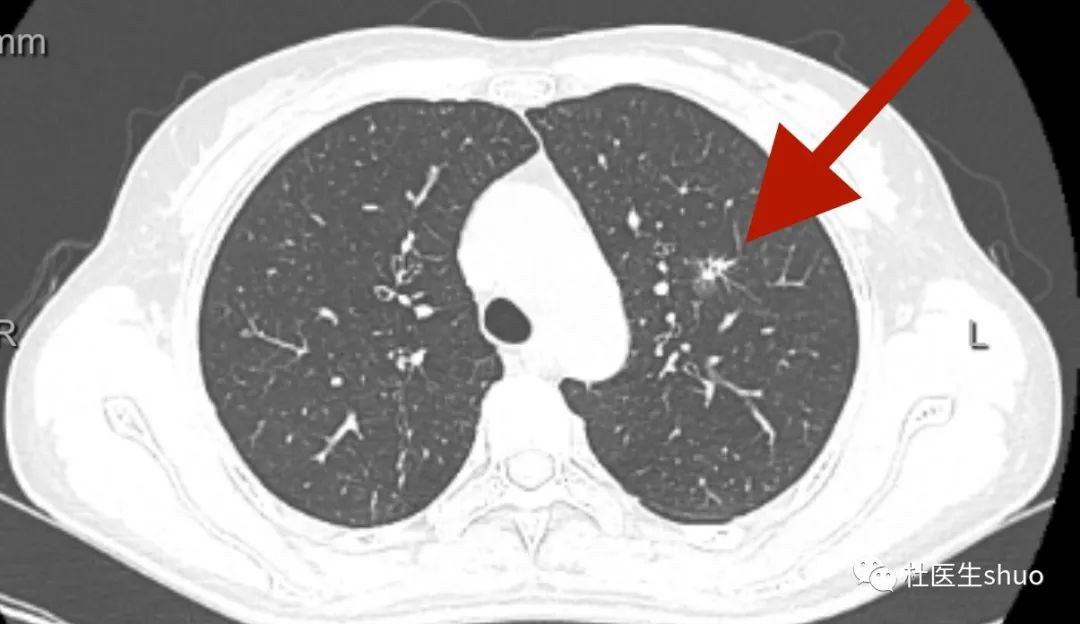

很多人体检胸部CT发现肺结节,咨询了医生,得到的结果是暂时不需要处理,定期复查即可。

首先你需要知道,你的结节是什么样的!

可分为实性结节、部分实性结节和磨玻璃结节。

三、磨玻璃结节: